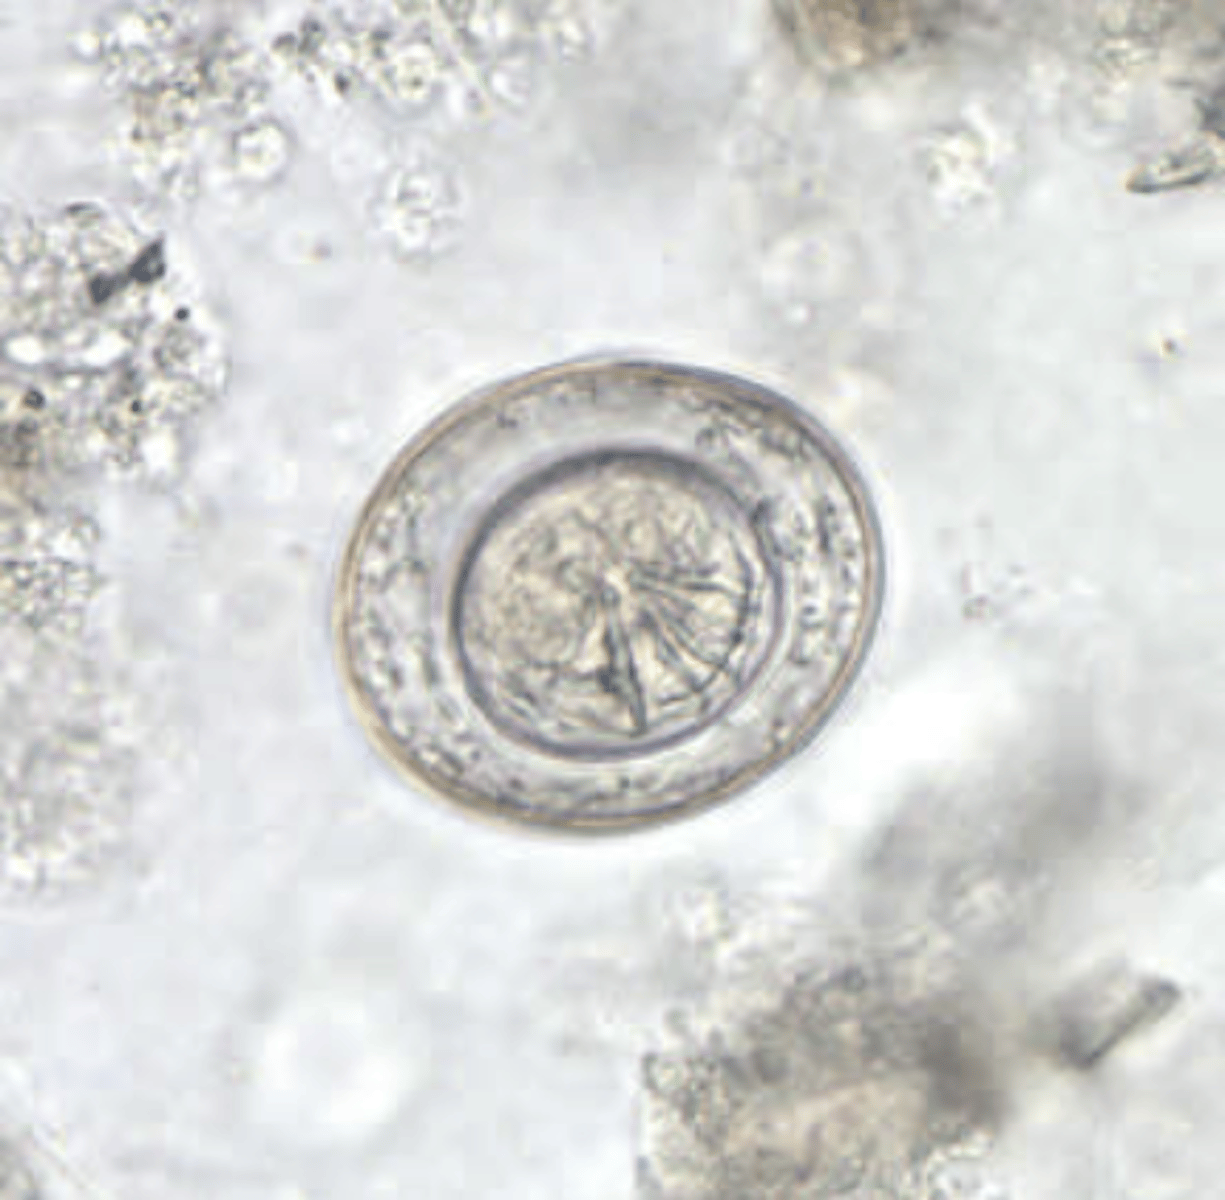

Hymenolepis nana